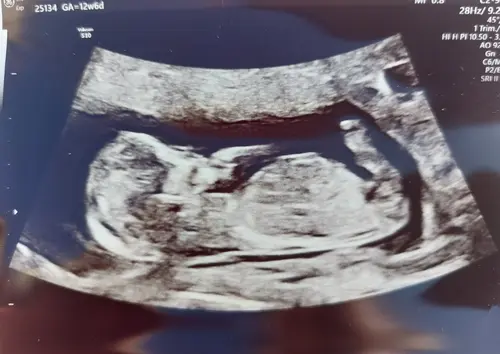

Ik heb 2 echo’s waarop je (volgens mij) de nub kan zien alleen nu zie ik op de ene een meisje en op de andere een jongen…… wat denken jullie? Dit is de eerste echo

Dit is een meisje. Op je andere echo is geen nub te zien

Ik dacht daar een bobbel te zien ipv streepje maar dat is dus geen nub? Ik was er eigenlijk al helemaal van overtuigd dat we een jongetje krijgen en nu bekeek ik de andere echo is goed en zag ik opeens een streepje 🤣

Dat is de nub, ook wel de clitoris in wording 🩷